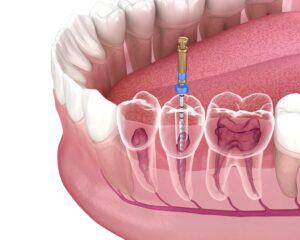

The physical makeup of your tooth includes an area called the pulp, which can be found in the centre under the enamel and dentin. This space houses nerves, connective tissue, and blood vessels, acting as one of the most important parts of your tooth. It’s a vital component that needs to be protected since damage to this area may lead to the decay of that tooth, and by extension, impact your other teeth and jaw.

If you are experiencing ongoing tooth pain that cannot be resolved through over-the-counter treatments, it’s possible you need a root canal. A visit to your dentist will confirm your need for this procedure, and they can book you an appointment that works for your schedule, although sooner is better than later. During the root canal, your dentist will numb the area before grinding down the tooth. They will then carefully remove the pulp and any residual tissue within the tooth. To prevent further damage, the tooth will then be sealed with a filling or a crown.

You might need a root canal for a few reasons. In any case, it is typically done because the pulp of your tooth is exposed and could easily become infected. Tooth decay, such as a cavity that has been untreated for some time may require a root canal procedure. An injured tooth that is chipped or cracked may also require this kind of restorative dentistry, or a tooth that has received too many dental procedures and is weak as a result. Ultimately, a root canal is done to save your tooth from falling out and potentially affecting other parts of your mouth.